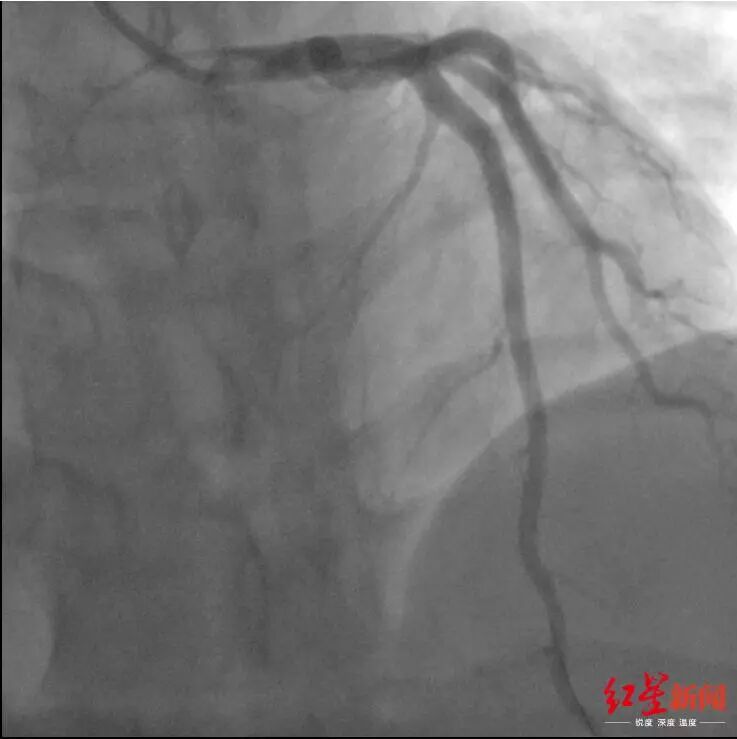

小蒲术前的冠脉造影显示 前降支血管严重堵塞

进行紧急冠脉造影,造影结果显示,原本应该粗大明显的冠脉血管前降支的显影只剩下1厘米左右。

“前降支被堵死了!”

李燕伟说到,前降支又被叫做生命支,承担着左心室的供血功能,这根血管被堵,意味着生命线被堵